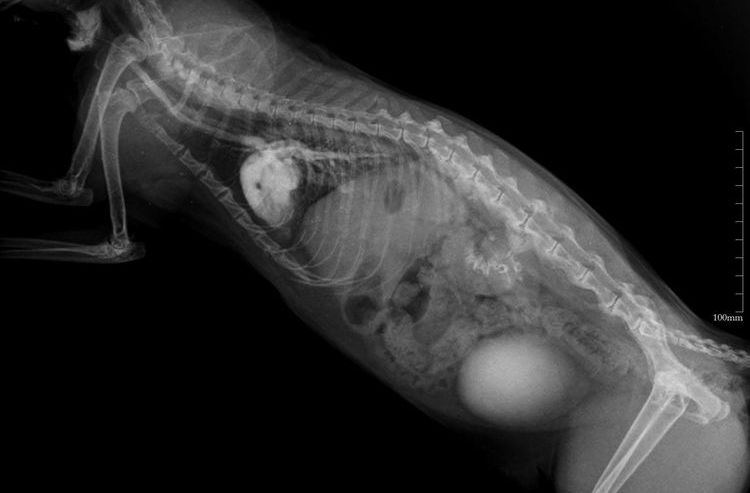

- Radiographie, échographie et IRM – pour détecter les tumeurs ou les troubles du fonctionnement des organes et des systèmes.